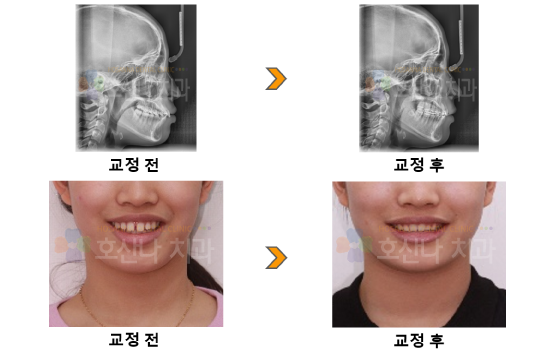

교정돌출입, space closing, deep bite + gummy smile 교정 시술 증례

< 돌출입, space closing , deep bite + gummy smile 교정 >

10대 female, 돌출입과 치아 사이의 공간을 모으길 원하는 환자분

1) Skeletal CL I deep bite

2) Lip protrusion

3) Spacing / #11-21 barrel shape / #12,22 small size

4) Gummy smile

5) Lt full II canine, molarrelation

3. 교정 후 결과

1) Space closing

2) 입술 돌출감 개선

3) Normal Overbite/Overjet

교정전 입술의 돌출감도 심했지만 전치부 치아 사이의 심한 공간 그리고 웃을 때 잇몸이 과도하게 보이는  gymmy smile을 가지고 있습니다.

전치부 사이의 공간은 치아의 사이즈가 작기도 했으나 최대한 교정으로 마무리하길 원하셔서 최대한 발치 하지 않고 현재 있는 공간을 모두 후방으로 견인함으로써 돌출도 개선하기로 합니다.

교정 후 돌출이 개선됨으로써 자연스러운 입매와 스마일을 보여주네요.

잇몸이 증식이 있으므로 치아의 길이를 길게 해주는 잇몸 성형이 추천되지만 아직 어리니 나중에 졸업하면 물방울 레이저로 인해 개선하면 더 예쁘겠네요.^^

5.교정기간

1y 7m